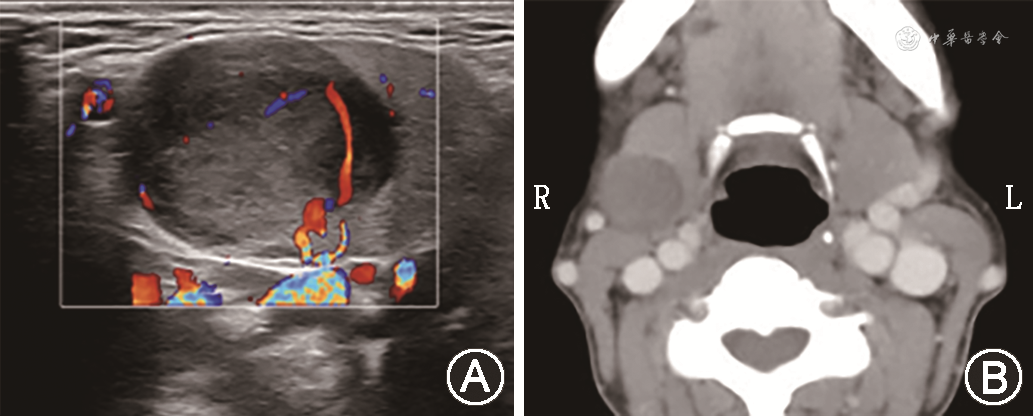

患者女性,46岁,因“发现右侧颌下区肿物39年余”于2021年5月11日入院。专科查体:右侧颌下区可触及一大小约3 cm圆形肿物,质中偏软,活动度可,无红肿、触痛。彩超提示右侧颌下腺低回声团块,大小约2.1 cm×1.6 cm×2.1 cm,形态规则,边界清楚(图1A)。CT提示右侧颌下腺占位,大小约1.9 cm×2.0 cm,倾向于良性病变(图1B)。患者及家属有较高美观需求,排除禁忌证后全身麻醉下行腔镜下经腋下入路右侧颌下腺及肿物切除术。患者采取垫肩仰卧位,头偏向健侧约45°,患侧上肢自然外展90°,显露患侧腋窝(图2A)。手术区域为下颌角、二腹肌前腹至腋窝切口之间的类矩形区域。做顺腋窝自然皱褶切口,在腋窝切口靠近乳腺侧约“两横指”、腋前线略下方作为戳卡的置入位置。切开皮下脂肪层后逐层分离至胸大肌外侧缘上端。置入悬吊拉钩,进行腔镜下操作。沿手术区域分离胸大肌皮瓣,越过锁骨,显露胸锁乳突肌后缘。沿胸锁乳突肌表面逐渐分离时注意主动规避或显露保护头侧的颈外静脉(图2B)。显露带状肌外侧缘后,沿颈动脉三角区域继续分离直至显露二腹肌前后腹,显露颌下腺及肿瘤,肿瘤位于腺体的后方,无腺体外侵犯(图2C)。凝闭颌下腺导管,解剖保护舌神经,在二腹肌后腹深面血管夹夹闭面动脉近心端(图2D)。即可将颌下腺深面整体游离。向下牵拉颌下腺,在颌下腺上缘和下颌骨下缘之间钝性分离,解剖保护面神经下颌缘支。寻找并显露面动、静脉远心端,超声刀凝闭。继续游离颌下腺上份,最终完整切除颌下腺及肿瘤(图2E)。标本袋取出肿瘤,冲洗止血,放置引流管,缝合腋窝切口(图2F)。患者术中出血小于10 ml,手术时长约90 min。病理确诊为多形性腺瘤。术后3 d总引流量为110 ml,患者于术后第3天出院。术后随访5个月,切口甲级愈合,未见面瘫,无颈部及上肢疼痛或活动障碍,无颈部皮肤感觉减退或麻木感,未出现口腔唾液分泌减少等症状(图3)。